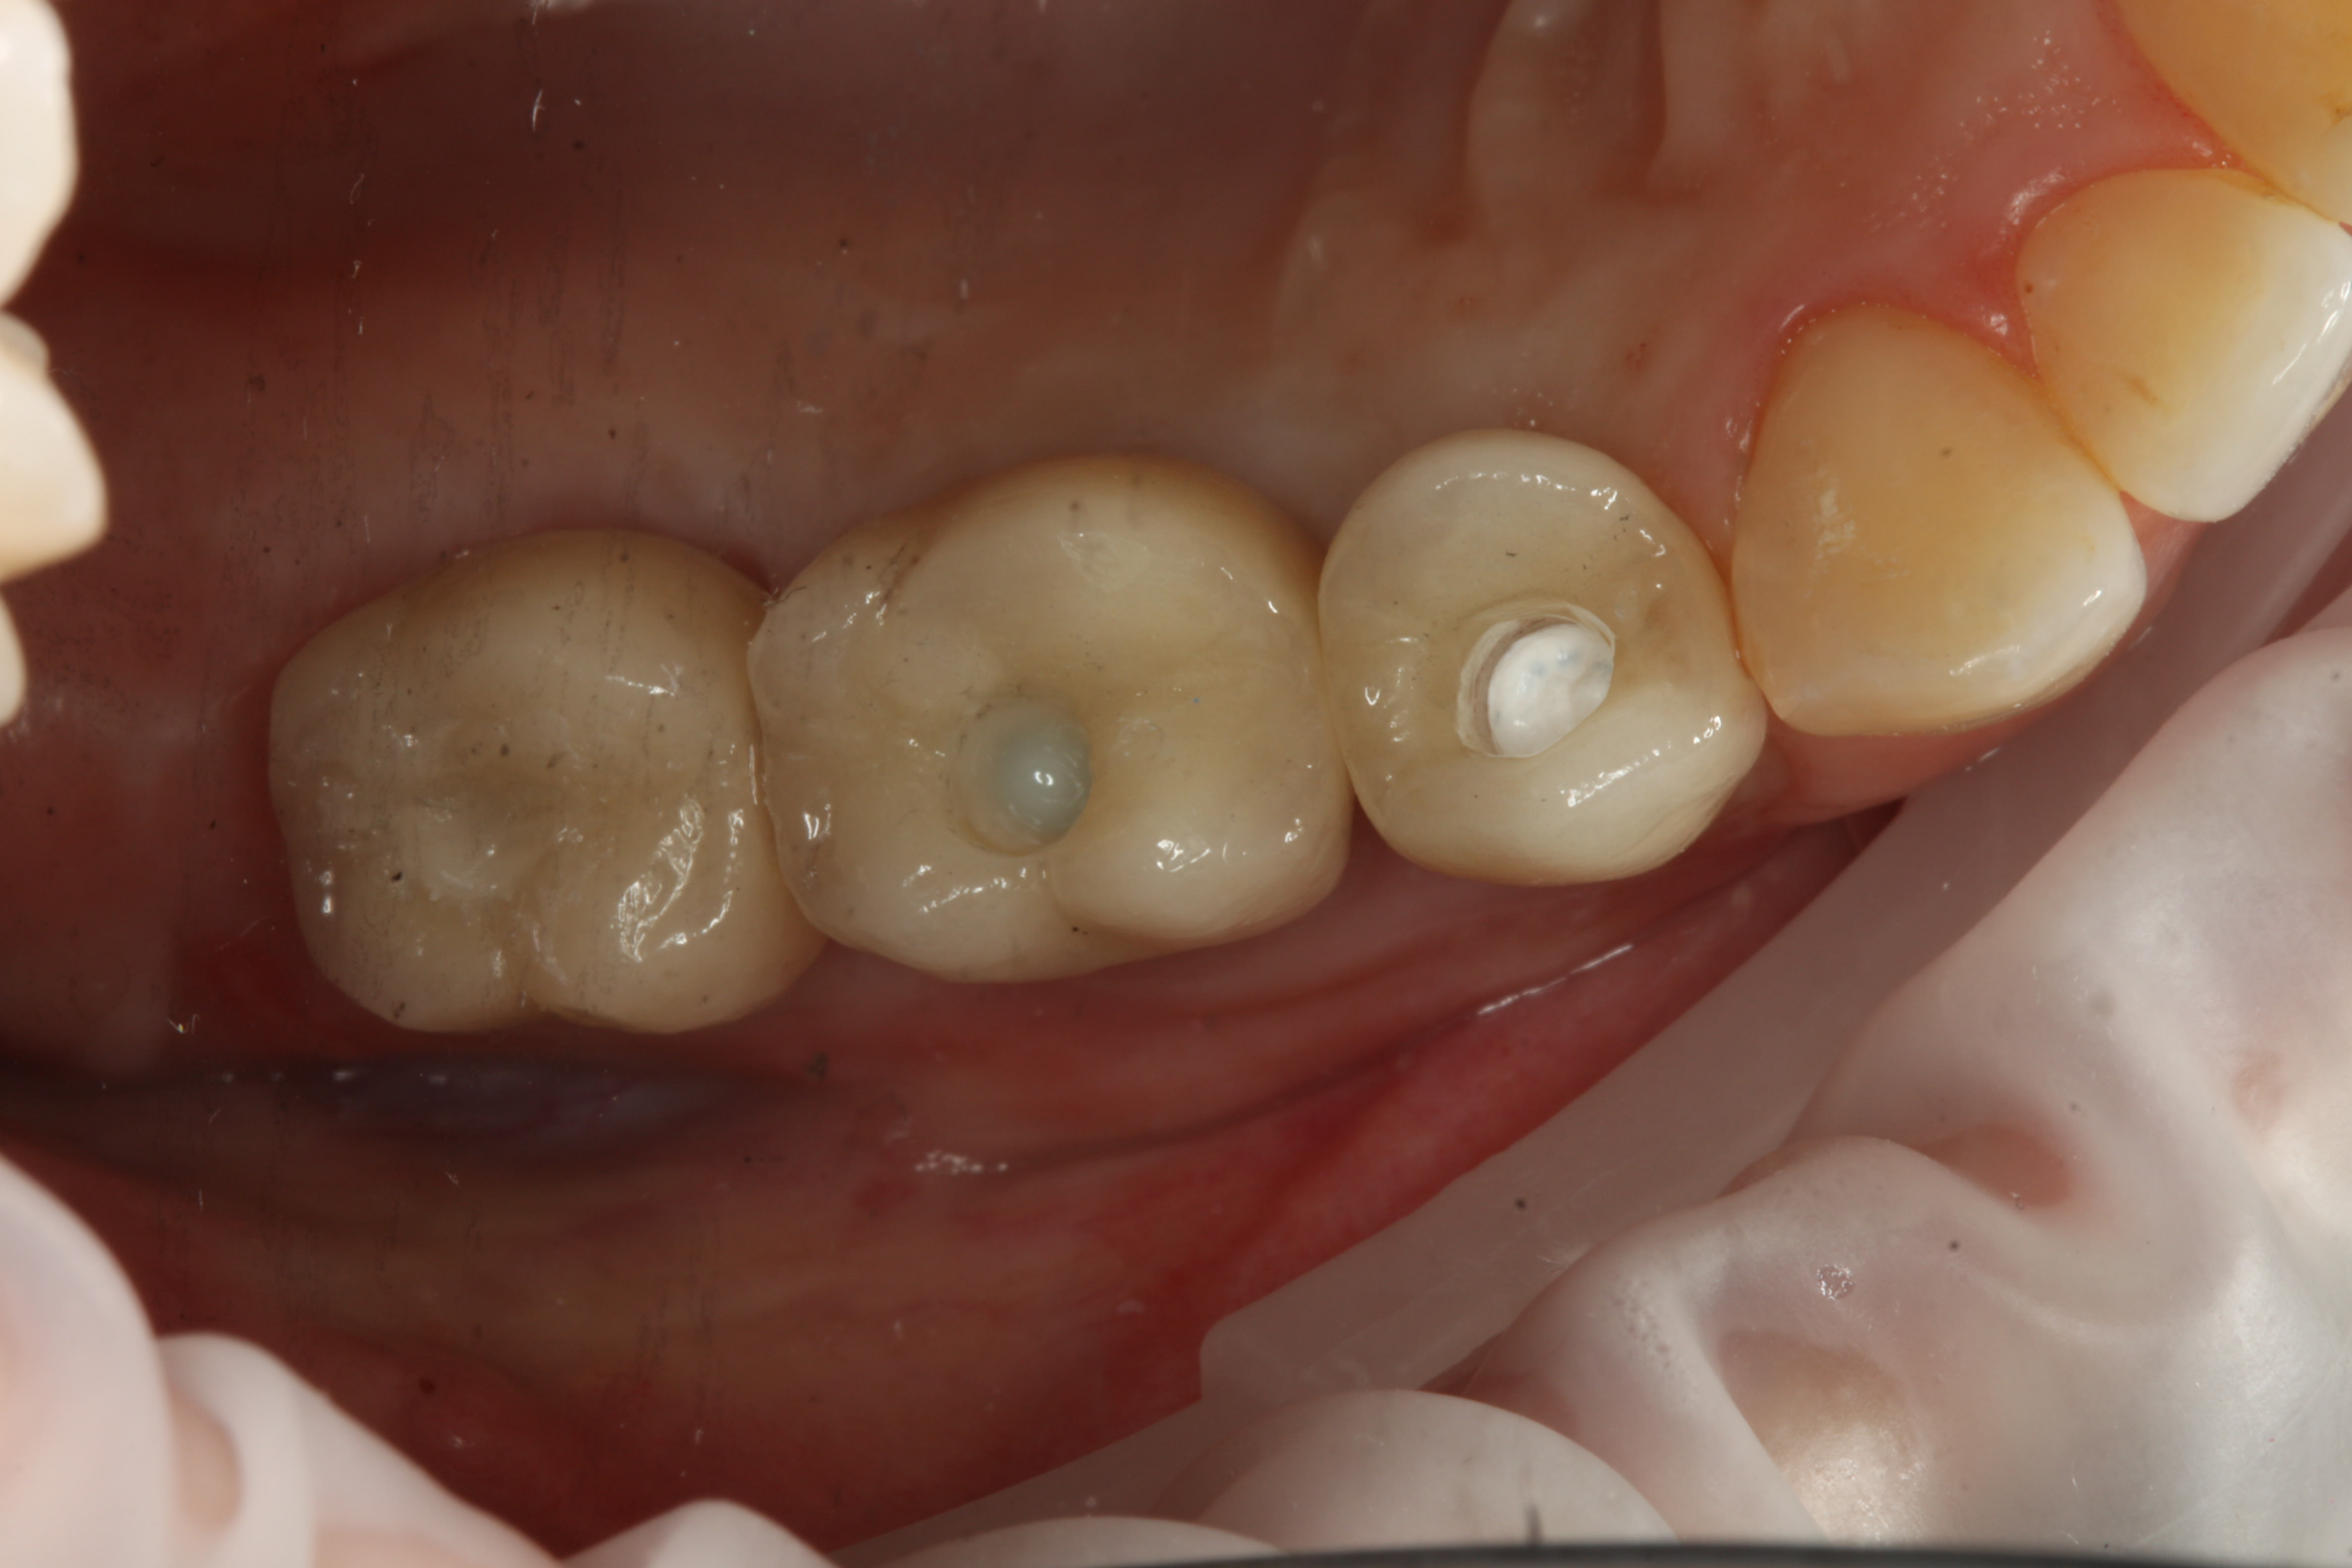

Avec couronne zircone, c'est déjà plus facile.

Ensuite, teflon dans le puit, compo flow blanc opaque (ionoseal)et Esthelite OA3.

Même recette sur tout mes cas, peut importe la couleur de la couronne, ça marche ;-)

Photo avec 14 teflon, 15 plus Ionoseal et 16 plus Esthelite OA3

Sorry pour le miroir super sale :-(